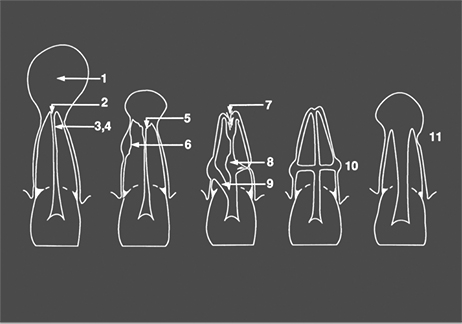

- For complicated cases involving traumatic injury and other instances where extended calcium hydroxide therapy is indicated.

- Treats periapical lesions, abscesses, traumatic injuries, root resorption, root perforations, and weeping canals

- Stimulates apexification and apexogenesis